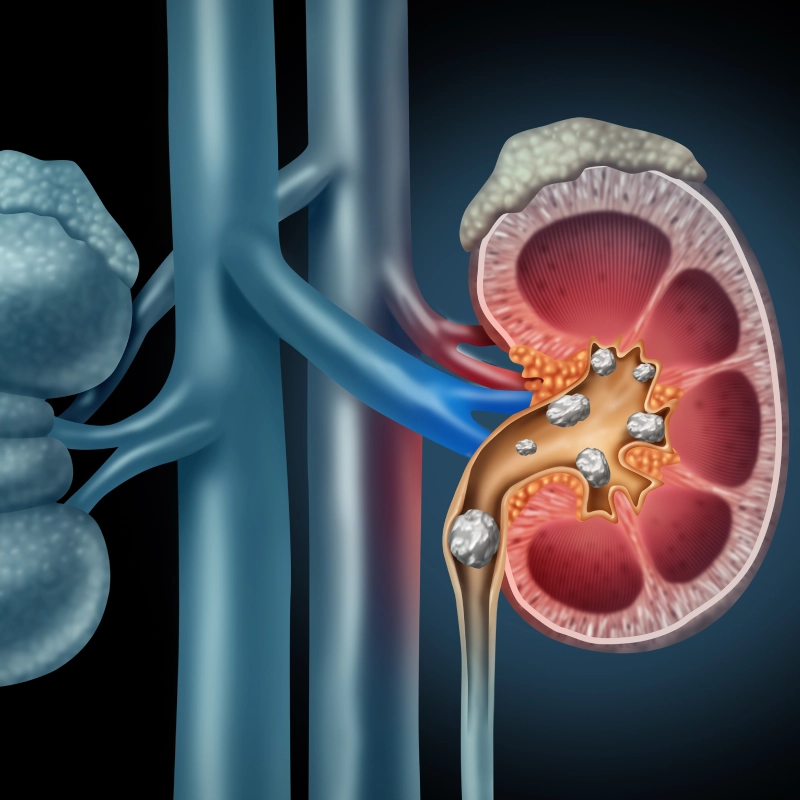

خطة التصريف الشاملة.. كيف تحمين كليتيكِ من الأملاح والترسبات بطرق طبيعية؟

استكمالاً لرحلة الوقاية من حصوات الكلى في 2026، يجب أن ننظر إلى “كيمياء البول” وكيف يمكننا جعلها بيئة طاردة للحصوات بدلاً من كونها بيئة حاضنة لها. هناك خطوات تكميلية لا تقل أهمية عن شرب الماء، تتعلق بنوعية المشروبات والعادات اليومية التي قد تبدو بسيطة ولكن مفعولها في حماية نسيج الكلى مذهل. إليكِ بقية الخطوات السبعة للوقاية الشاملة.

5. سحر الحمضيات (قوة السترات): الليمون والبرتقال ليسا فقط للفيتامينات، بل هما “منظفات طبيعية” للكلى. يحتوي الليمون على مادة “السترات” (Citrate)، وهي مادة كيميائية تمنع بلورات الكالسيوم من الالتصاق ببعضها لتكوين حصوة. إضافة عصرة ليمون طازجة على الماء يومياً هي واحدة من أذكى العادات الصحية التي يحبها أطباؤك في 2026، لأنها ترفع قلوية البول وتذيب الأملاح الصغيرة أولاً بأول.

6. الحذر من “الأوكسالات” العالية: بعض الأطعمة الصحية جداً مثل السبانخ، البنجر، المكسرات، والشوكولاتة الداكنة، تحتوي على نسب عالية من “الأوكسالات”. إذا كنتِ ممن تتكون لديهم حصوات بشكل متكرر، لا تحرمي نفسكِ منها، ولكن تناولي معها مصدراً للكالسيوم (مثل قطعة جبن أو كوب زبادي). هذا التكتيك يضمن ارتباط الكالسيوم بالأوكسالات في المعدة وليس في الكلى، مما يحميكِ من خطر التبلور.

7. الحفاظ على وزن صحي وتجنب السكر: الأبحاث في 2026 تربط بقوة بين “مقاومة الإنسولين” وزيادة حموضة البول، مما يمهد الطريق لحصوات حمض اليوريك. السكريات المضافة والمشروبات الغازية تزيد من إفراز الكالسيوم في البول وتزيد الالتهابات. الحفاظ على وزن مثالي وممارسة الرياضة يحسن من كفاءة الدورة الدموية الكلوية ويساعد الجسم على طرد الفضلات بانتظام وبدون مجهود إضافي.

نصيحة أخيرة للمستقبل: إذا شعرتِ بألم في الجنب أو تغير في لون البول، لا تنتظري. الفحص الدوري في 2026 أصبح سهلاً جداً بالموجات الصوتية (السونار)، والكشف المبكر عن “الرمال الكلوية” يغنيكِ عن آلام الحصوات الكبيرة. كليتاكِ هما مصفاة جسمكِ الغالية، فاعتني بهما بالماء والخضروات والاعتدال، لتنعمي بحياة مريحة وخالية من الأوجاع.